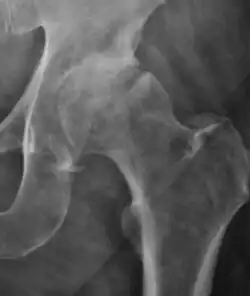

Plain radiography allows us to categorize the hip as normal or dysplastic or with impingement signs (pincer, cam, or a combination of both). Besides these, pathologic processes like osteoarthritis, inflammatory diseases, infection, or tumors can also be identified (Figure 1).[1]

Figure 1.

-

Radiography in normal hip -

X-ray in pincer impingement type of hip dysplasia -

X-ray of cam -

Hip in osteoarthritis -

Septic arthritis

In adults, one of the main indications for radiographs is the detection of osteoarthritic changes (Figure 1(e)). Nevertheless, radiographs usually detect advanced osteoarthritis that can be graded according to the Tönnis classifications. The grading system ranges from 0 to 3, where 0 shows no sign of osteoarthritis. Intermediate grade 1 shows mild sclerosis of the head and acetabulum, slight joint space narrowing, and marginal osteophyte lipping. Grade 2 presents with small cysts in the femoral head or acetabulum, moderate joint space narrowing, and moderate loss of sphericity of the femoral head. Grade 3 is the severest form of osteoarthritis, which manifests as severe narrowing of the joint space, large subchondral cyst with productive bone changes that may lead to deformity of the bone components of the joint, while secondary osteoarthritis due to calcium pyrophosphate deposition can be diagnosed when calcification of hyaline cartilage and fibrocartilage is detected.[1]

There are other pathological conditions that can affect the hip joint and radiographs help to make the appropriate diagnosis. Acute bacterial septic arthritis can be diagnosed by radiographs when a fast regional osteoporosis and destructive monoarticular process develops (Figure 1(f)). In case of tuberculous or brucella arthritis it is manifested as a slow progressive process, and diagnosis may be delayed.[1]

Synovial chondromatosis can be confidently diagnosed by X-ray when calcified cartilaginous chondromas are seen. However, other synovial proliferative processes, such as pigmented villonodular synovitis, require MRI for accurate diagnosis, although noncalcified synovitis can be suspected in radiographs by indirect signs, such as soft tissue swelling and/or erosions in the femoral head, femoral neck, or acetabulum (Figure 7).[1]